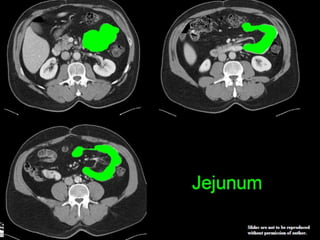

Small Intestine  Thebody’s major digestive organ  Site of nutrient absorption into the blood  Muscular tube extending from the pyloric sphincter to the ileocecal valve  Suspended from the posterior abdominal wall by the mesentery

• 49.

Subdivisions of theSmall Intestine  Duodenum(25cm) Attached to the stomach Curves around the head of the pancreas Fixed retroperitoneal structure  Jejunum (2.5m) Attaches anteriorly to the duodenum  Ileum (3.5m) Extends from jejunum to large intestine